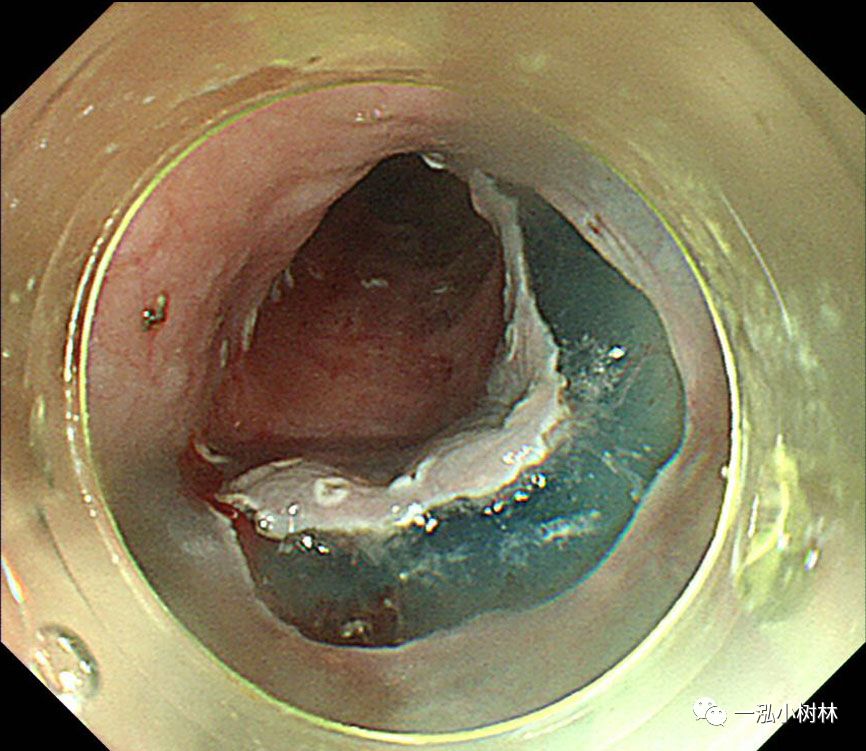

图3 碘染色:病变呈不规则拒染区